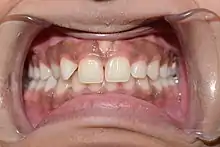

اللثة جزء من الأنسجة الرخوة المبطنة للفم. تحيط بالأسنان وتوفر ختمًا حولها. على عكس بطانات الأنسجة الرخوة للشفاه والخدود، فإن معظم اللثة مرتبطة بإحكام بالعظم الأساسي مما يساعد على مقاومة احتكاك الطعام الذي يمر فوقها. وبالتالي عندما يكون صحيًا، فإنه يمثل حاجزًا فعالًا أمام وابل الإهانات اللثوية للأنسجة العميقة. عادة ما تكون اللثة الصحية وردية مرجانية في الأشخاص ذوي البشرة الفاتحة، وقد تكون أغمق بشكل طبيعي مع تصبغ الميلانين.

خصائص اللثة السليمة

اللون

لون اللثة الصحي غالبا ما يوصف بأنه زهري رائق، الألوان الأخرى تدل على إصابات مرضية كالأحمر القاني في التهاب اللثة الحاد والأحمر الغامق إلى الأحمر المزرق في التهاب اللثة المزمن، ويمكن أن تتسبب الرواسب الزائدة من الميلانين في ظهور بقع داكنة أو بقع على اللثة ( فرط تصبغ اللثة بالميلانين)، خاصة عند قاعدة الحليمات بين الأسنان. كما يمكن أن يسبب التدخين أو تعاطي المخدرات تغير اللون أيضًا (مثل " فم الميثامفيتامين "). وعلى الرغم من وصف اللثة الصحية باللون الوردي المرجاني، إلا أن الاختلاف في درجة لون اللثة الصحية من شخص لآخر ممكن أن يكون نتيجة عوامل مثل: سمك اللثة ودرجة التقرن في الظهارة، ودرجة تدفق الدم إلى اللثة، ونسبة تصبغ الجلد الطبيعي، وأيضاً الإصابة بأمراض عضوية ما، وتناول أدوية معينة من شأنها التأثير لون اللثة.[4] وعلى الرغم من ذلك، تلعب الاختلافات العرقية دورا في درجة تلون اللثة في الحالة الصحية، بمعنى أنه وفي العرق الأسمر مثلا قد نشاهد اللثة بلون غامق بل وحتى مصطبغة بلون أسود من صباغ الميلانين دون أن يعني ذلك أي تظاهرة مرضية، ولذلك نعتمد أكثر في تشخيص المرض اللِّـثَـوِي على تجانس اللون أكثر من اللون بحد ذاته.

محيط شكل

اللثة الصحية لها محيط أملس ومستدق كحد السكين حول عنق السن. وتكون الحليمات شاغلة تماما كامل المسافة بين السنية وبشكل مثلثي، أما عندما تلتهب اللثة وتورم فتصبح الحواف مدورة منتفخة.

الملمس

اللثة الصحية لها نسيج قوي مقاوم للحركة، وغالبًا ما يظهر نسيج السطح تنقيطًا على السطح . من ناحية أخرى، غالبًا ما تكون اللثة غير الصحية منتفخة وأقل صلابة. اللثة الصحية لها ملمس يشبه قشر البرتقال بسبب التنقيط.

القوام

قوام اللثة السليمة قوام متماسك مرن مقاوم للحركة وسطح اللثة الملتصقة محبب ومفصص كقشر البرتقال، في حالات الالتهاب الحاد يصبح رخو اسفنجياً، وفي حالات التهاب اللثة المزمن يصبح القوام متماسكاً ليفياً بأكثر من الطبيعي.

رد فعل للاضطراب

عادة لا يكون للثة السليمة أي رد فعل تجاه الاضطرابات الطبيعية مثل تنظيف الأسنان بالفرشاة أو فحص دواعم الأسنان . على العكس من ذلك، ستظهر اللثة غير الصحية نزيفًا عند الفحص (BOP) و / أو الإفرازات القيحية .